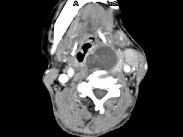

问题 女,64岁,发现双甲状腺肿大一月余,CT如图所示,最可能诊断为 ( )

选项 A、甲状腺转移癌 B、甲状腺结核 C、甲状腺腺瘤 D、甲状腺癌并淋巴结转移 E、结节性甲状腺肿

答案 D